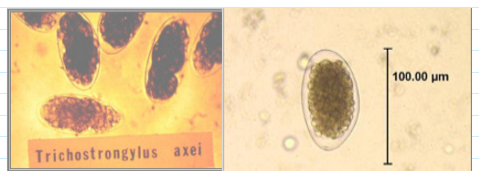

trichostrongylus eggs

Must differentiate from hookworm eggs

78-98 x 40-50 um

Larger, elongated compared to hookworm

Slightly pointed